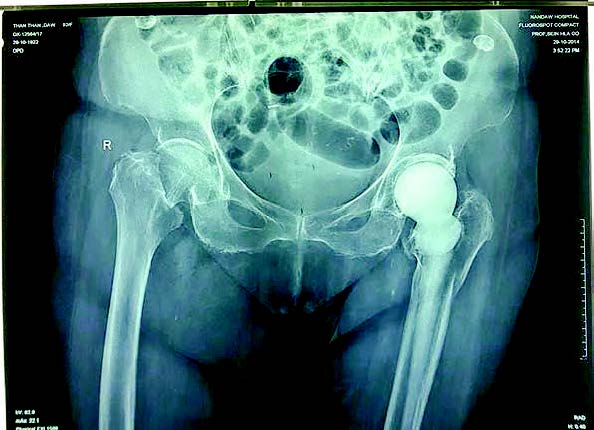

In January 1960, my late father first used an ivory prosthesis to replace the fractured thigh bone of an 83-year-old Burmese Buddhist nun, Daw Punya. He had to go to an ivory carver in the city of Mandalay to sculpt an ivory hip prosthesis. After his return from the University of Pennsylvania, doing his post-graduate studies for 3 1/2 years, my father was posted as Head of the Department of Orthopaedic Surgery at Mandalay General Hospital from November 1958 to June 1975. And he was posted as chief of orthopaedic surgery at Rangoon (now Yangon) General Hospital from June 1975 until his retirement in October 1980. From 1960 to 1980, Dr San Baw and his junior colleagues operated upon and inserted ivory hip prostheses to replace the fractured thigh bones of patients whose ages ranged from 13 to 87. Definitely one, if not two, persons who Dr San Baw inserted ivory hip prostheses are still alive as of mid-April 2025. On or about December 1969, a person from a village near Mandalay at the age of about thirteen was inserted with an ivory hip prostheses by my late father and his junior colleagues in an operation which lasted for about four hours (as told to me by the patient herself). The patient’s name is Daw Than Htay (born around November 1956). Up till about mid-2021, she lived in a village about a hundred and fifty miles from Mandalay. She currently lives in a monastery in Mandalay. Sometime in 2024, an X Ray was taken of her left hip (about 55 years after her insertion of the ivory prosthesis), and even though the prosthesis was broken, there has been a creeping substitution or ‘biological bonding’ between bone and ivory, the 2024 X-rays show.

In the context of Burma from the 1960s to the early 1990s, ivory was a cheaper material to use as implants or prostheses to replace fractured thigh bones. Starting from 1959 in Mandalay, Dr San Baw studied the physical, mechanical, chemical and biological properties of ivory for about a year before he inserted it as a replacement on the 83-year-old Burmese Buddhist nun Daw Punya in January 1960. He consulted a physics professor and a zoology professor when investigating the physical, mechanical and biological properties of ivory. It must be emphasized that when my father was using ivory to replace hip fractures from the 1960s to early 1980s, there was no (no) killing of elephants. Only when elephants died say carrying logs after living their natural lives, was the ivory extracted from the elephants. Indeed, about ten years after Dr San Baw passed away in December 1984, his junior colleagues continued to use ivory prostheses as hip implants. One such patient, now deceased, Daw (Mrs, honorific) Than Than (May 1923-May 2023) (a different person from Daw Than Htay mentioned above) had a fall and fractured her left hip sometime after 1990. Professor U Meik, a junior colleague of Dr San Baw, an orthopaedic surgeon in Mandalay, used an ivory hip prosthesis in the early 1990s as a hip replacement for Daw Than Than. In October 2014, the elderly lady broke her right hip, and another orthopaedic surgeon replaced it with a metal hip prosthesis

In August 2017, Clinical Orthopaedics Journal published the case of the only person in the world then over the age of ninety years who had an ivory prosthesis in her left hip and metal prostheses in her right hip, with photos of X-rays. On the cover of the Journal, the photos of ivory hip prostheses that yours truly sent to the Journal were ‘touched up’ and displayed.